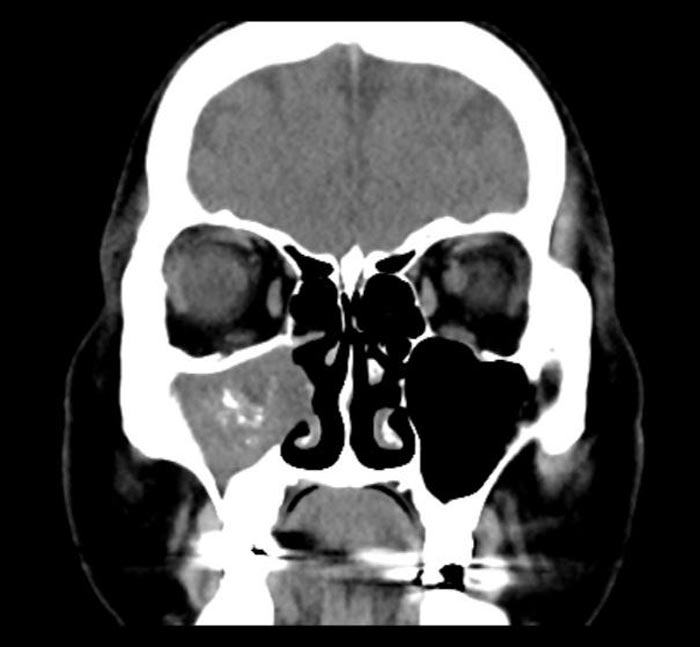

ดร.เฉิน เผยว่า หลังจากตรวจในเบื้องต้นเขาคาดว่าอาการของคนไข้น่าจะไม่ใช่แค่ไซนัสอักเสบเฉียบพลันแบบธรรมดา จึงได้ทำการตรวจซีทีสแกน จนได้พบว่า โพรงอากาศข้างจมูก หรือไซนัสฝั่งขวาของเธอถูกอุดตันด้วย ก้อนเชื้อราขนาดใหญ่ จึงวินิจฉัยว่า คนไข้หญิงรายนี้เป็น "ไซนัสอักเสบจากเชื้อรา" ต้องรักษาด้วยการผ่าตัด โดยแพทย์ได้นำก้อนเสมหะที่รวมอยู่กับเชื้อราออกจากโพรงจมูกของคนไข้อย่างระมัดระวัง จนสามารถนำออกมาได้ทั้งหมด ซึ่งพบว่ามีจำนวนมากอย่างน่าตกใจ

ภาพจาก เฟซบุ๊ก 耳鼻喉科 陳世璽醫師